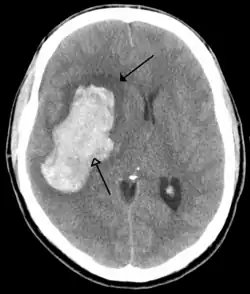

Hersenbloedingen

Hersenbloedingen kennen twee hoofdtypen:[12][13]

- Intracerebrale bloeding, waarbij de bloeding in de hersenen ontstaat, bijvoorbeeld als een ader knapt. Er kan onderscheid gemaakt worden tussen een intraparenchymale bloeding (bloeding in het functionele hersenweefsel) of intraventriculaire bloeding (bloeding in het ventrikelstelsel).

- Subarachnoïdale bloeding, waarbij de bloeding buiten de hersenen, maar wel binnen de schedel ontstaat. Dit vindt plaats tussen het spinnenwebvlies en het zachte hersenvlies. Dit laatste vlies ligt meteen tegen de hersencellen aan en is het zachtste van de drie hersenvliezen.

Hersenbloedingen ontstaan als een bloedvat in de hersenen openbarst. Als dit gebeurt krijgen de hersencellen die normaal door dit bloedvat van bloed worden voorzien geen voedingsstoffen en zuurstof meer en sterven af. Het bloed dat uit het bloedvat vloeit duwt het normale hersenweefsel weg. Door de samendrukking van hersenweefsel dat hierdoor kan optreden treedt verdere beschadiging op. Belangrijke oorzaken van hersenbloedingen zijn hoge bloeddruk, afwijkingen van de bloedvaten zoals aneurysmata en AVM's en hersentumoren.